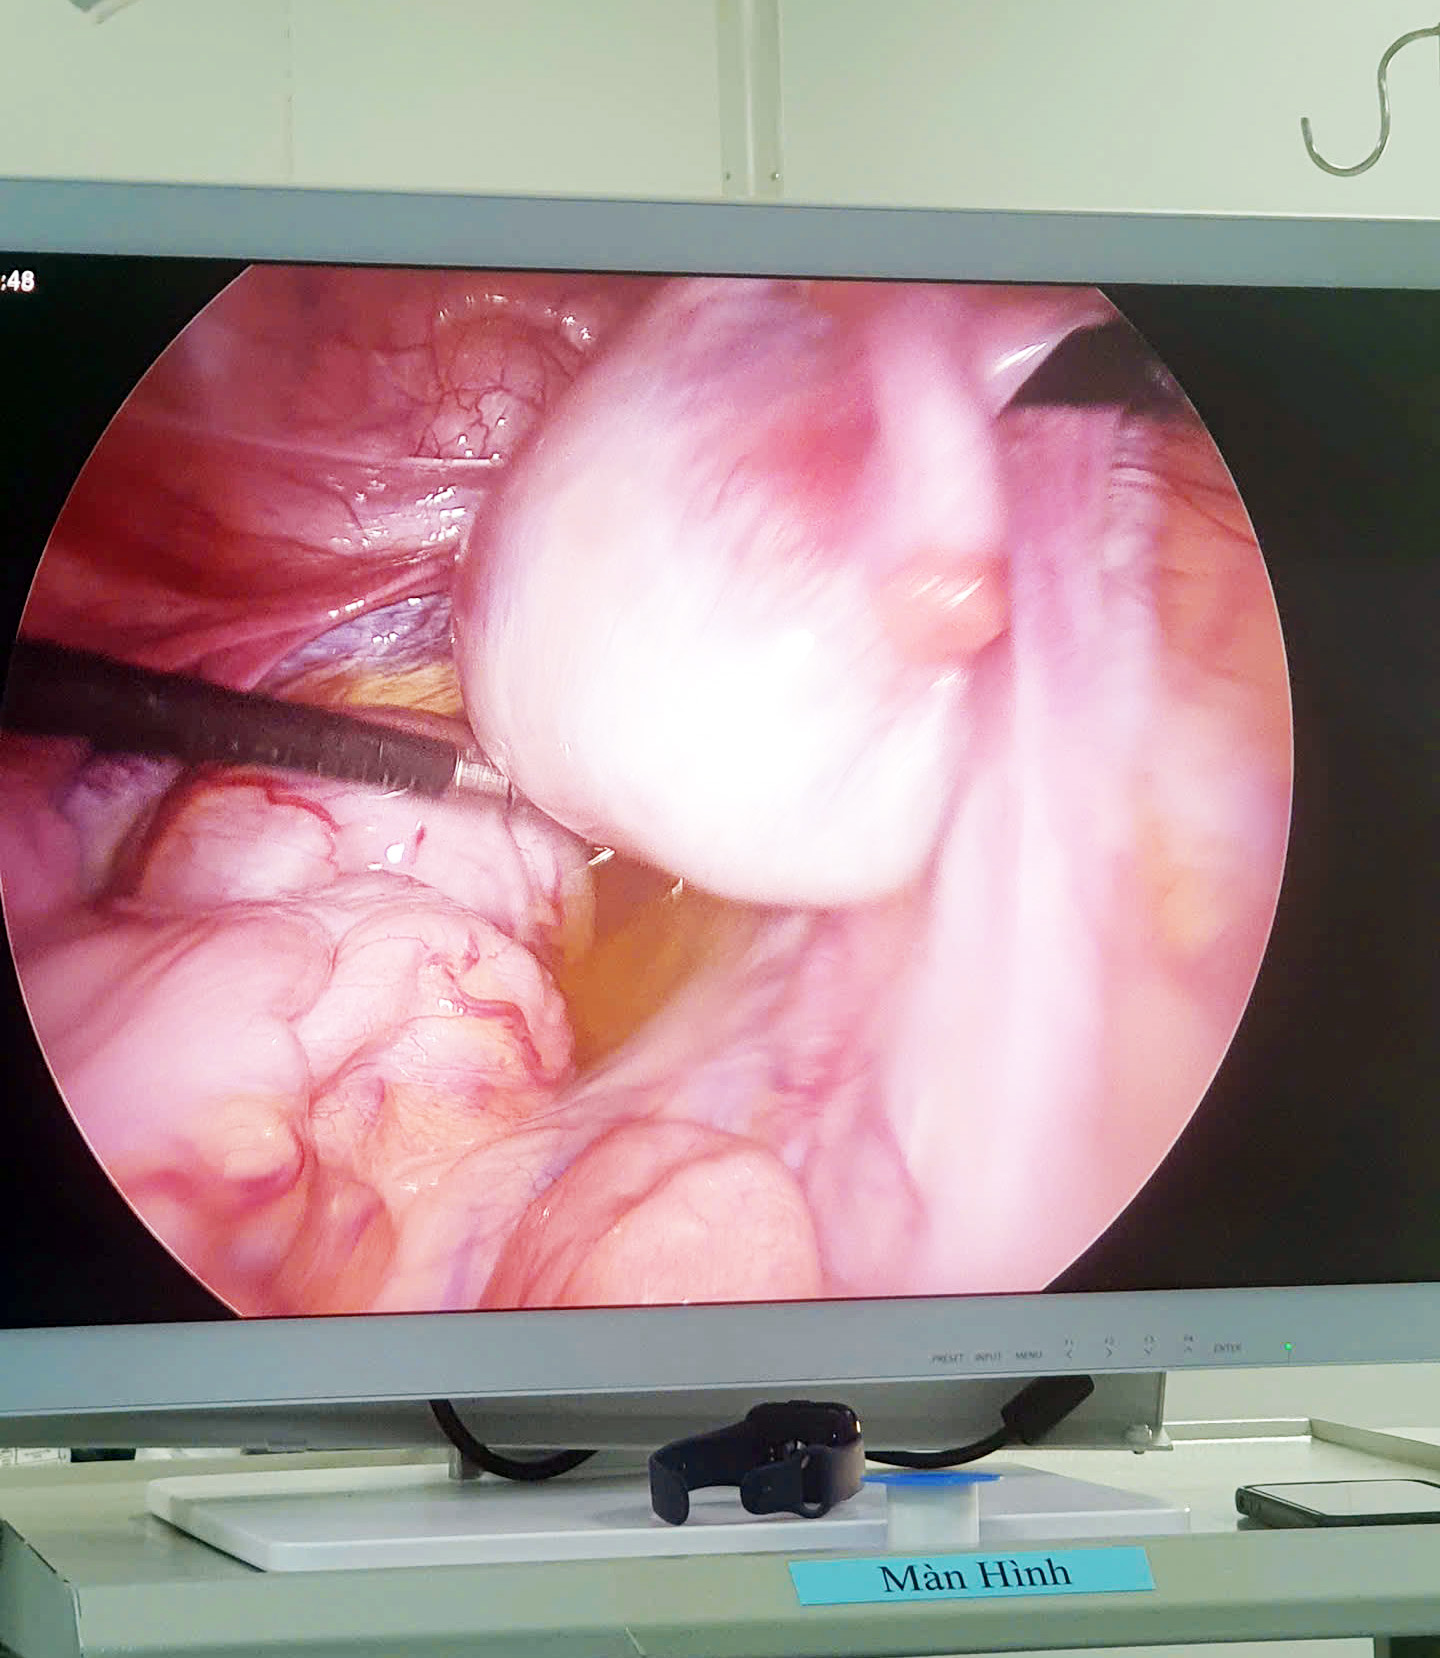

Với tinh thần khẩn trương, các bác sĩ đã nhanh chóng hội chẩn toàn viện, huy động các chuyên khoa Sản, Sơ sinh, Gây mê hồi tỉnh, ngoại khoa, huyết học cùng phối hợp chuyển mổ cấp cứu lấy thai an toàn cho sản phụ và con, tiến hành gỡ dính phức tạp tử cung-bàng quang-thành bụng, bóc tách hạ bàng quang, lấy thai, xử trí các tổn thương và cầm máu tại vị trí rau cài răng lược, khâu mũi transverse-B Lynch, bảo tồn được tử cung cho sản phụ.